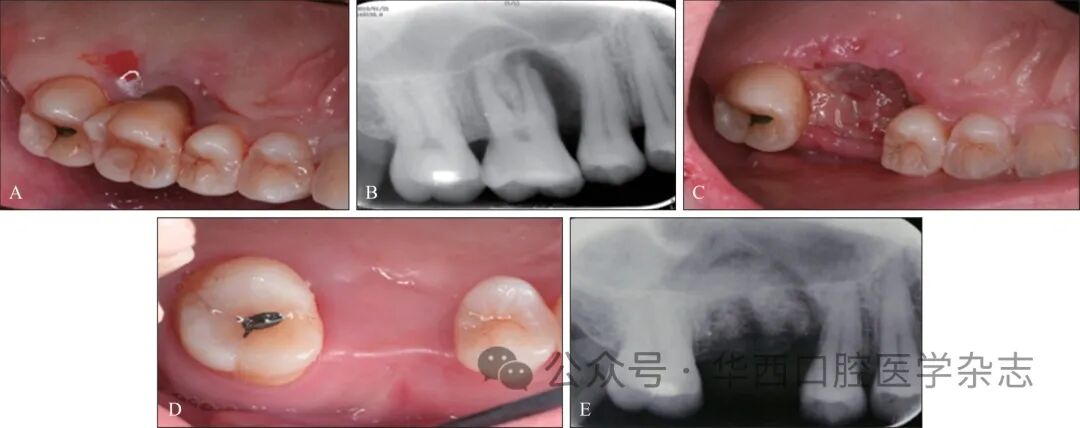

因此,目前的研究和临床实践循证均主张为了提高后期修复的质量、便利性、可靠性等,对于预后差考虑拔除的患牙,应在拔牙同期或早期根据评估和预判,进行积极的局部干预,以最大限度保留原牙槽窝(嵴)的高度、宽度,以及周边软组织量(最主要是角化黏膜量)[14-15];因为此时进行硬组织和软组织的增量或保存都是较为容易的,不增加更多创伤,创面封闭性更好;可以变后期被动修复为主动设计(图3)。

▲图 316牙如拔除后按常规等待创面自然恢复,预期有软硬组织的凹陷性后果风险,给后期缺牙修复带来不便和困难,应给予主动干预▲Fig 3If extracting tooth 16 and waiting for naturally recover as usual, there is a risk of concave consequences in soft and hard tissues, which may cause inconvenience and difficulty in the later restoration, so active intervention should be givenA:拔牙前口内照;B:拔牙前X线片;C:位点保存术后2周口内照;D:位点保存术后4月口内照;E:位点保存术后4月X线片。